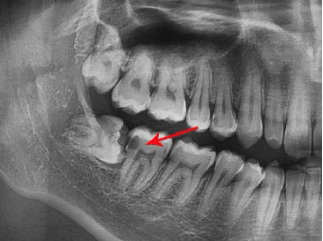

3、邻牙龋坏

倾斜生长的智齿和相邻的第二磨牙呈不正常的邻接关系,两颗牙齿之间经常会出现食物嵌塞现象,食物容易发生嵌塞,长期如此导致细菌聚集,造成邻牙龋坏的发生。

4、邻牙牙体吸收

朝向邻牙生长的智齿常无法正常萌出,并长期在第二磨牙远中,这将导致第二磨牙牙体组织吸收,最终缩短第二磨牙的使用寿命。